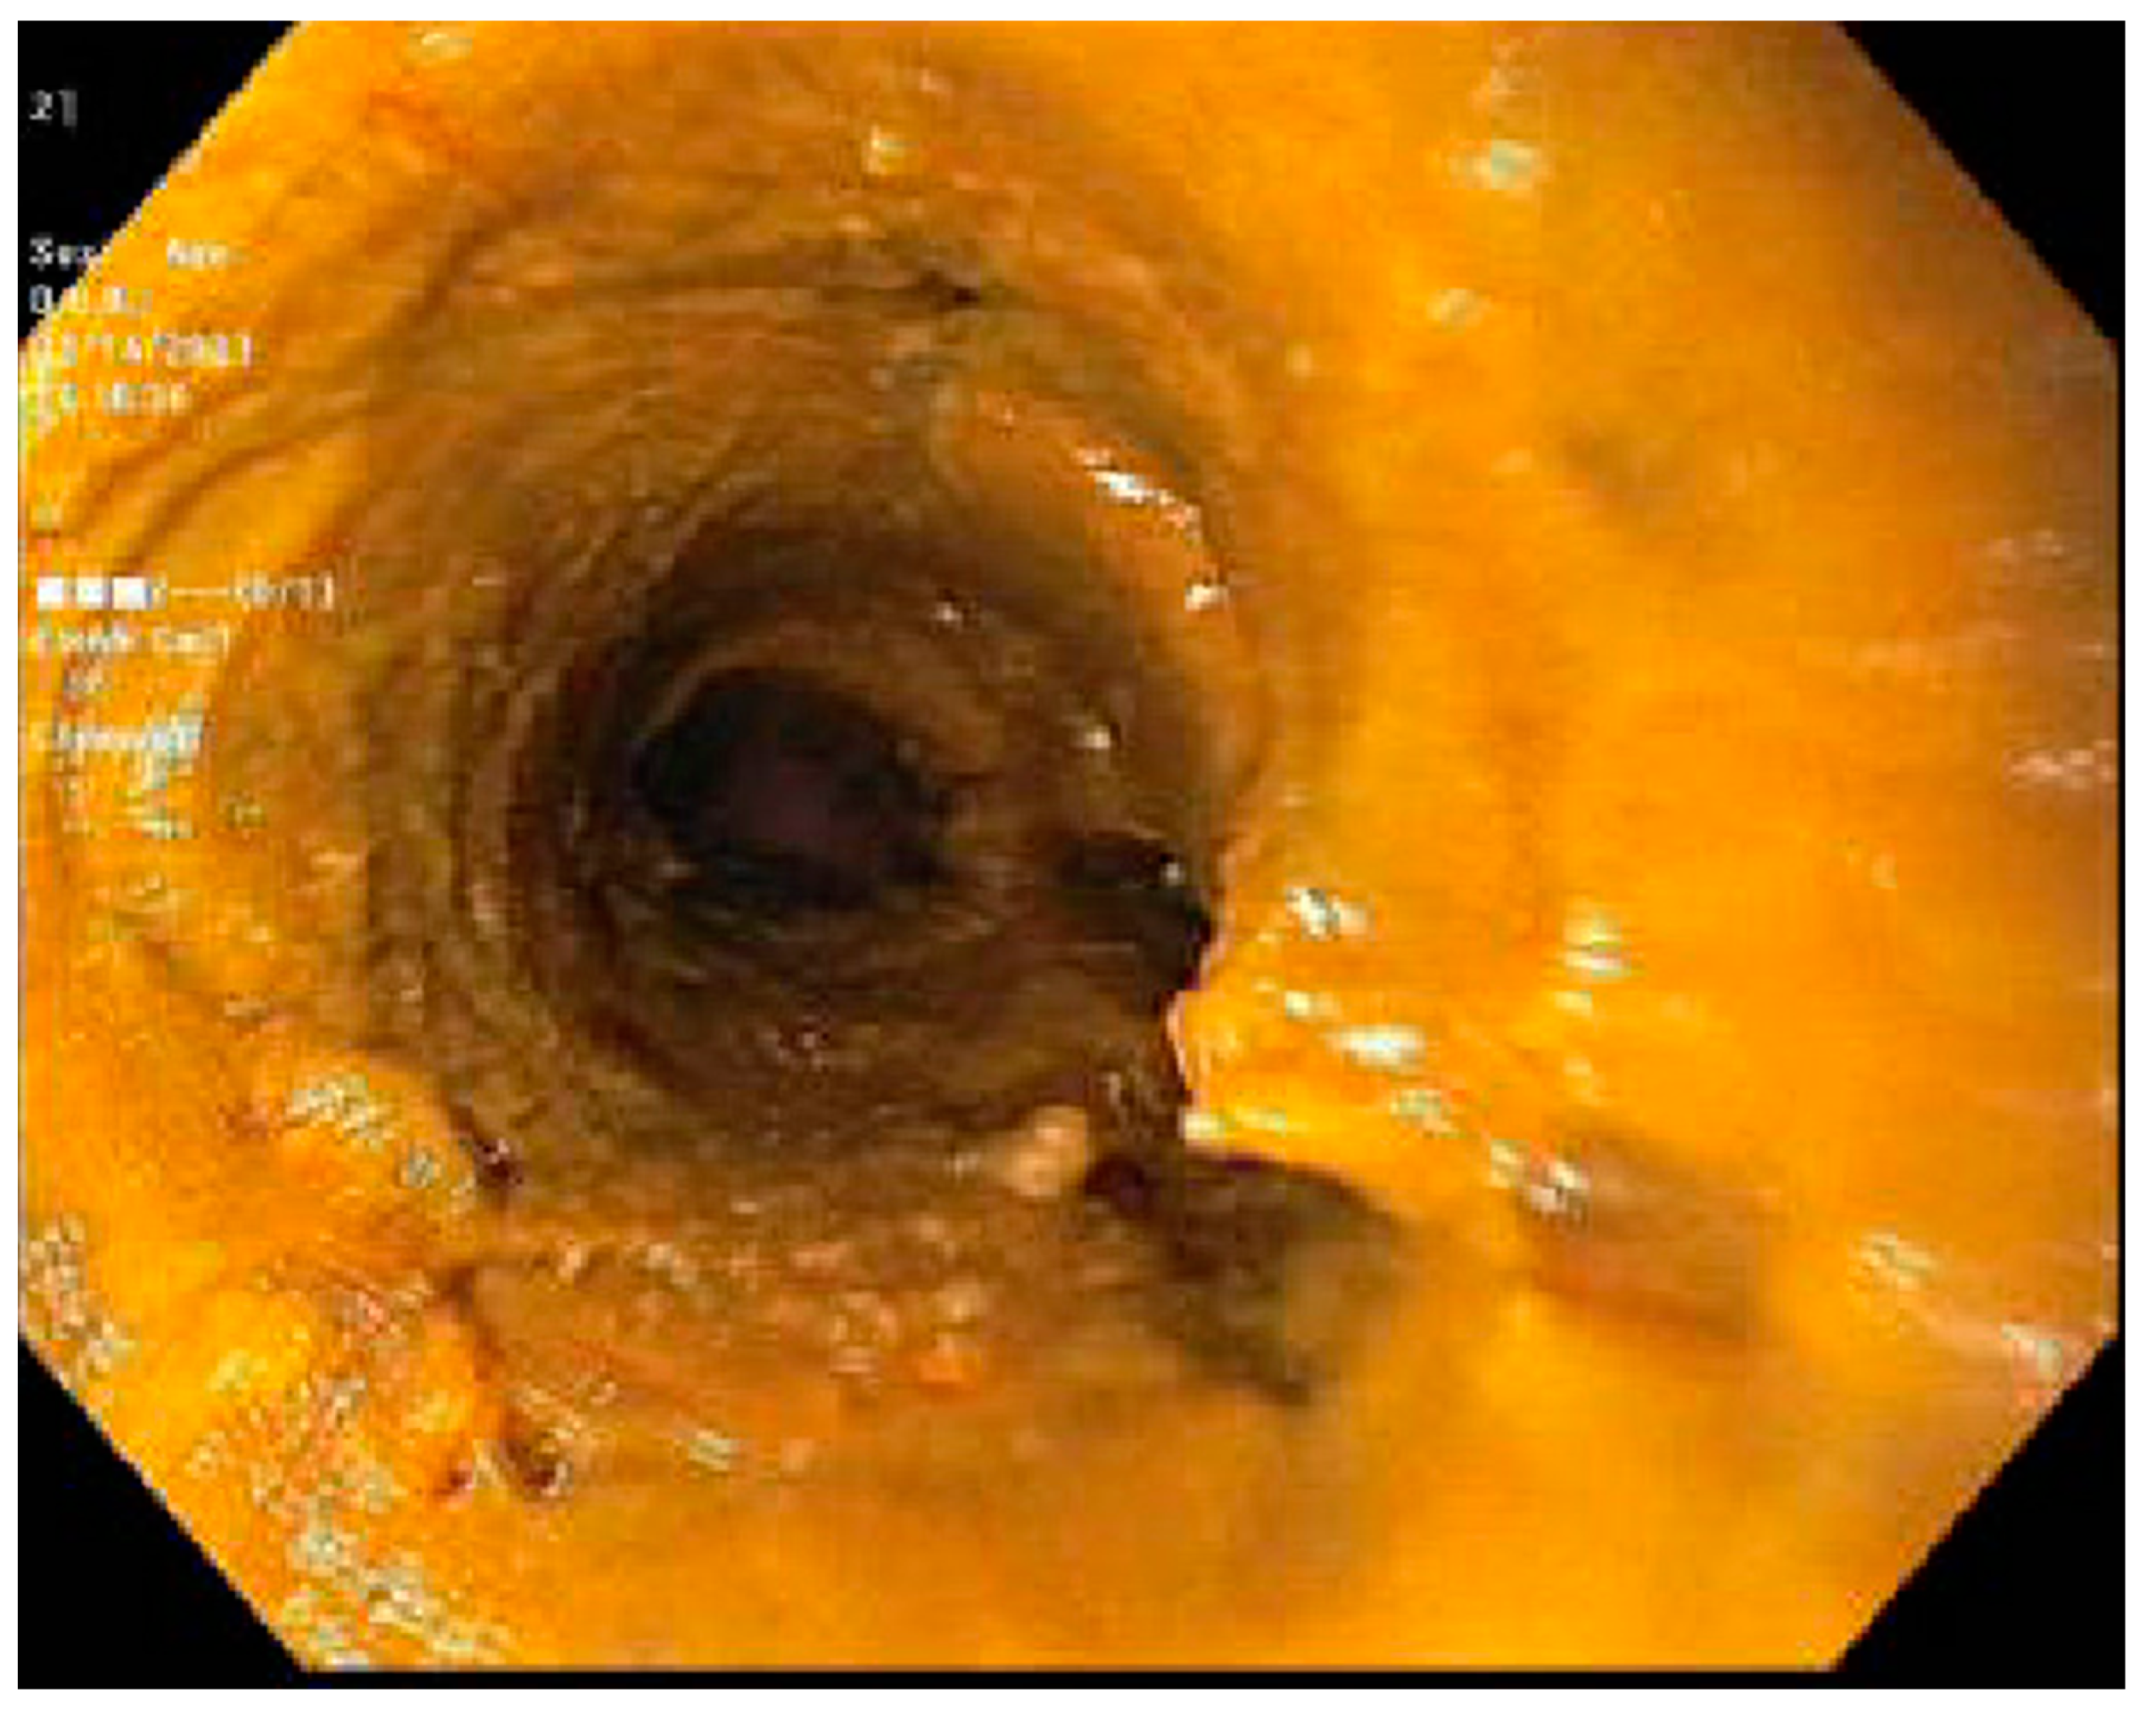

- Cruz-Correa, M.; Poonawala, A.; Abraham, S.C.; Wu, T.T.; Zahurak, M.; Vogelsang, G.; Kalloo, A.N.; Lee, L.A. Endoscopic findings predict the histologic diagnosis in gastrointestinal graft-versus-host disease. Endoscopy 2002, 34, 808–813. [Google Scholar] [CrossRef]

- Oomori, S.; Takagi, S.; Kikuchi, T.; Utsunomiya, K.; Yokoyama, H.; Negoro, K.; Tohmiya, Y.; Aihara, H.; Yamada, M.; Takahashi, S.; et al. Significance of Colonoscopy in Patients with Intestinal Graft-Versus-Host Disease after Hematopoietic Stem Cell Transplantation. Endoscopy 2005, 37, 346–350. [Google Scholar] [CrossRef] [PubMed]